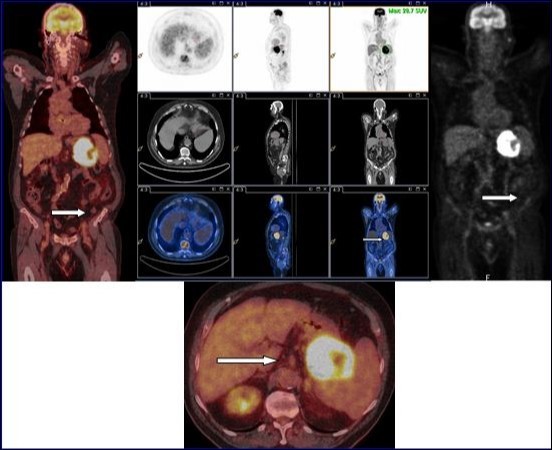

18F-FDG PET-CT with injection of intravenous iodinated contrast demonstrated an intense and diffuse hyper metabolism at the primary tumor of the stomach. No morphological or metabolic argument features of secondary manifestation of this tumor were observed in the whole-body (Figure 2). Partial gastrectomy with resection of the proximal 2/3 of the stomach, the spleen, the body and tail of pancreas and the left transverse colon was performed.

Figure 2.18F-FDG PET-CT with injection of intravenous iodinated contrast demonstrated an intense and diffuse hyper metabolism at the primary tumor of the stomach. No morphological or metabolic argument features of secondary manifestation of this tumor were observed in the whole-body.

18F-FDG PET-CT with injection of intravenous iodinated contrast demonstrated an intense and diffuse hyper metabolism at the primary tumor of the stomach. No morphological or metabolic argument features of secondary manifestation of this tumor were observed in the whole-body.